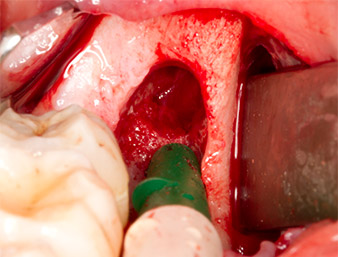

Pour obtenir un matériau autogène en vue du traitement ultérieur de la plaie, des fragments osseux sains sont collectés autour du reste radiculaire à l'aide d’un insert piézochirurgical (Piezomed B5) (Fig. 5).

Piezomed B5

Fig. 5 : Une élévation osseuse est pratiquée dans la région de l’alvéole à l'aide d’un instrument piézochirurgical en forme de burin (Piezomed B5). Cet os est utilisé comme matériau d’augmentation autologue après l’extraction du reste radiculaire (cf. Fig. 13 et 14).

Le tissu autogène est extrait à l’aide de la section en forme de racloir de la pièce active de l’insert et conservé dans un soluté physiologique isotonique jusqu’à utilisation ultérieure (cf. Fig. 13).